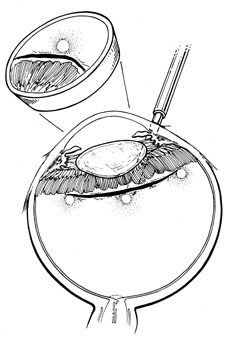

Scleral Dissection

After localization of all retinal breaks requiring support, a lamellar scleral undermining or scleral dissection is performed. The extent of dissection depends on the size of the intended buckle. It is recommended that the lamellar scleral dissection extend 3 mm posterior, 2 mm anterior, and 3 to 4 mm circumferentially beyond the retinal breaks.12 The dissection is begun with an incision parallel to the limbus at the posterior edge of the retinal breaks. The depth of the incision is considered appropriate if a thin gray layer of sclera remains over the choroid. The lamellar dissection is performed using a blunt dissector with traction on the reflected scleral flaps. Care is taken when dissecting posteriorly to the equator to avoid severing the vortex veins. Modifications of the posterior scleral flap often are necessary to avoid the vortex veins. The size of the scleral dissection is designed to accommodate the width plus the height of the desired implant (Fig. 25).

Fig. 25. A. Technique for scleral dissection. B. Recommended extent of scleral dissection for implant placement in relation to retinal breaks.